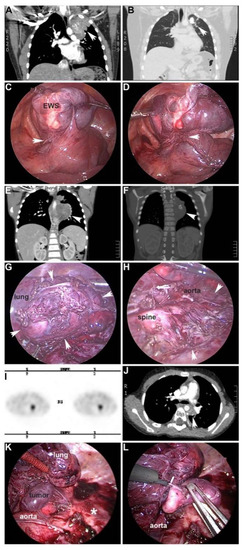

- Phelps, H.M.; Ayers, G.D.; Ndolo, J.M.; Dietrich, H.L.; Watson, K.D.; Hilmes, M.A.; Lovvorn, H.N., 3rd. Maintaining oncologic integrity with minimally invasive resection of pediatric embryonal tumors. Surgery 2018, 164, 333–343. [Google Scholar] [CrossRef] [PubMed]

| Phelps 2018 [14] | 17 laparoscopy | 17 resection 13 NBL 3 WT 1 RMS | 0 | No acute complications |

| 8 thoracoscopy | 8 resection 8 NBL | 0 | No acute complications | |